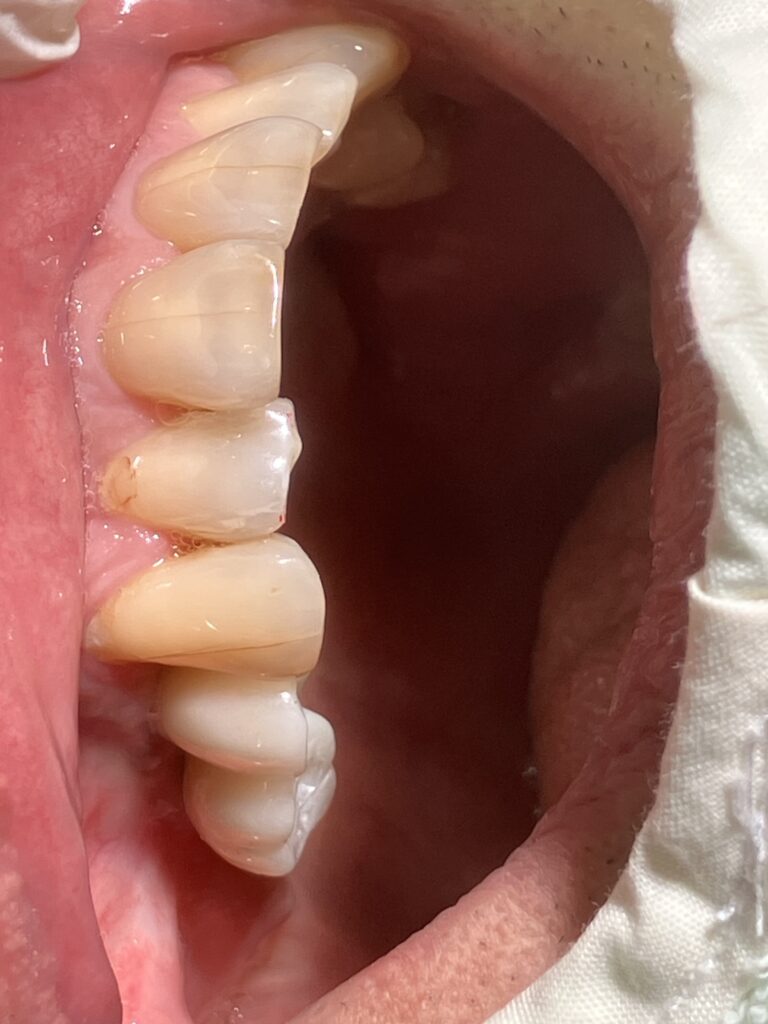

- 高い強度と耐久性: ジルコニアは非常に硬く、強い力がかかる奥歯にも適しています。割れたり欠けたりするリスクが低く、長持ちする傾向があります。

- プラークが付着しにくい: 表面が滑らかなため、 歯石やプラークが付着しにくく、 インプラント周囲炎のリスクを低減する可能性があります。

- 適合性の向上: CAD/CAMシステムを用いて精密に設計・製作されるため、歯との適合性が高いです。